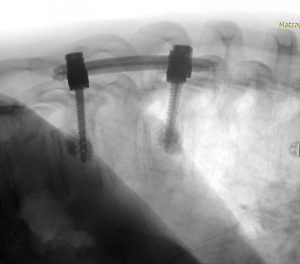

Διενεργήθη αποσυμπίεση του νωτιαίου μυελού μέσω πεταλεκτομίας και αφαίρεσης του ενδοκαναλικού τμήματος του όγκου και στη συνέχεια διαδερμική σπονδυλοδεσία με έγχυση οστικού τσιμέντου στα σπονδυλικά σώματα Θ9-Θ11

Στο συγκεκριμένο περιστατικό συνδυάστηκαν η ανοιχτή μέθοδος της πεταλεκτομίας για την αφαίρεση του ενδοκαναλικού τμήματος του όγκου και την αποσυμπίεση του νωτιαίου μυελού, με τη διαδερμική τεχνική της σπονδυλοδεσίας. Οι βίδες τοποθετήθηκαν με τη βοήθεια νευροπλοηγού το οποίο δίνει στο χειρουργό τη βεβαιότητα της απόλυτης ακρίβειας. Η διαδερμική τοποθέτηση των βιδών κράτησε την τομή μικρή, μειώνοντας σημαντικά τον μετεγχειρητικό πόνο και τον κίνδυνο φλεγμονής, επιτρέποντας στον ασθενή την άμεση κινητοποίηση και έξοδο από το νοσοκομείο. Η ενίσχυση των σπονδυλικών σωμάτων με οστικό τσιμέντο είχε πολλαπλό ρόλο: αφενός βοηθά στη σταθερότητα της σπονδυλοδεσίας (επιτρέποντας μας να έχουμε καλή στήριξη με “μικρή” σπονδυλοδεσία), αφετέρου προσέφερε σταθερότητα στον Θ9 σπόνδυλο ο οποίος είχε προσβληθεί από νόσο.